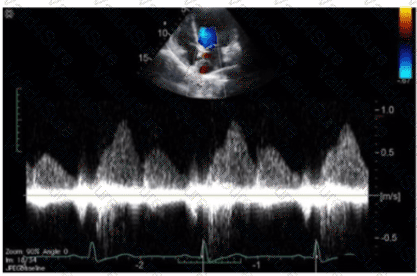

Question # 36

Which of the following does this Image represent?

A.

Mitral valve inflow

B.

Tricuspid valve inflow

C.

Hepatic vein Doppler

D.

Pulmonary vein Doppler